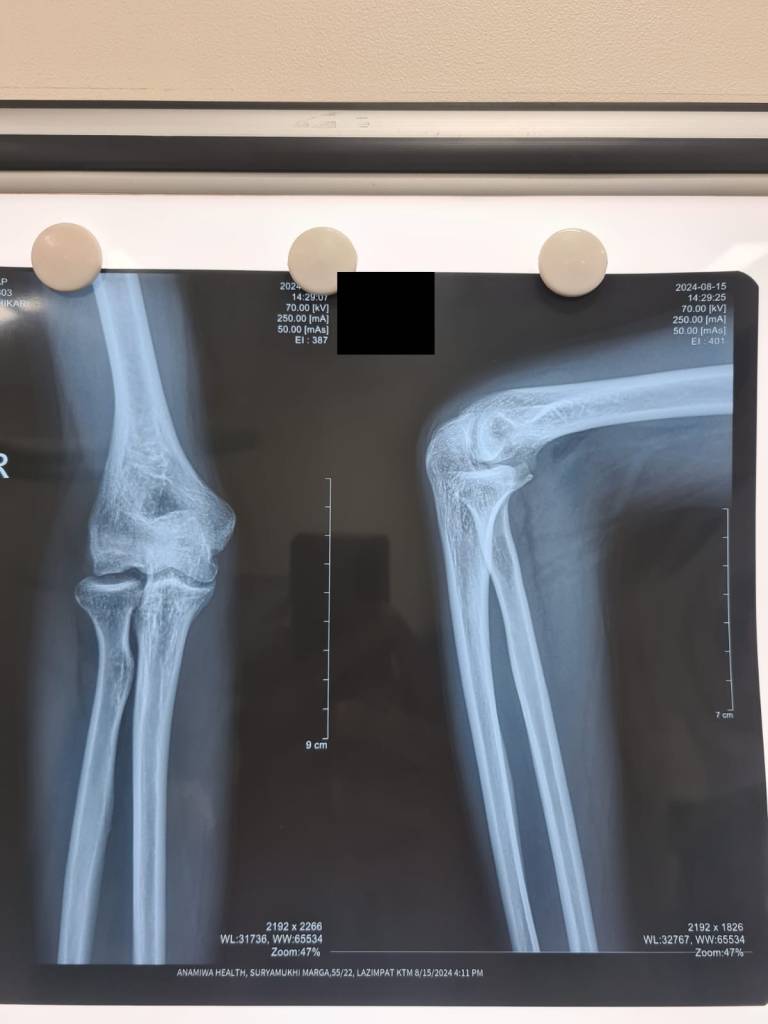

A young man with previous history of Panner’s disease presented at our clinic. The patient experienced a locking sensation in his elbow during movement. No obvious deformity such as an osteochondrosis was observed via X-ray imaging. However, during clinical examination, the orthopaedic team noted a disturbance during movement in the joint. After consideration of the patient’s history, we decided to perform a surgical exploration, during which the osteochondral fragment was successfully identified and removed. Panner’s disease, which refers to osteochondrosis of the capitellum of the humerus, is observed in children between ages 4 to 10, and is typically self-limiting. In this particular individual, the disease was not resolved; instead, the osteochondrosis remained loose in the joint, creating a locking sensation in the joint during movement.

This case highlights the importance of high-quality clinical examination. Even or especially when X-ray or other imaging does not corroborate the patient’s complaints, nothing can replace attentive clinical examination.